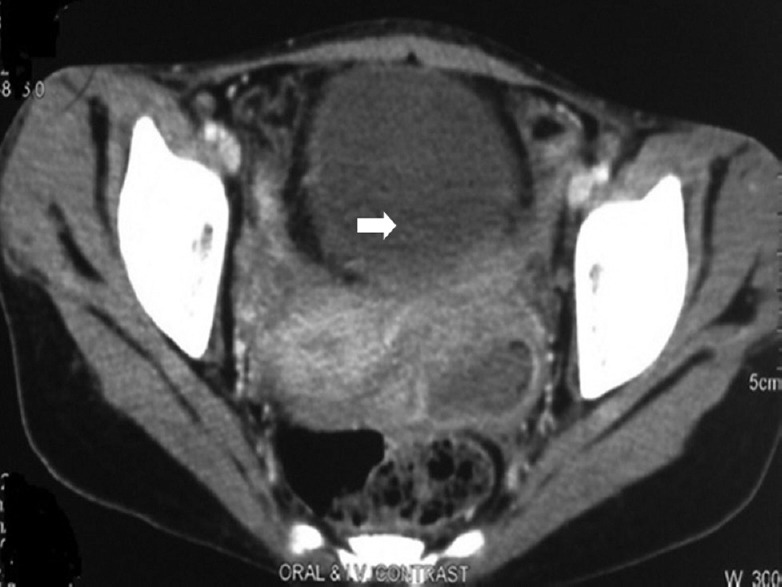

Computerized axial tomography (CAT) scan (Fig. 1) may show masses in abdomen and pelvis with ascites, thickened and enhanced peritoneum, with lesions in the abdominal viscera and lymph node46. Magnetic resonance imaging (MRI) has a higher resolution and may show tubo-ovarian masses. Unilateral or bilateral tubo-ovarian masses, hydrosalpinx, adnexal cysts or tuberculous deposits on peritoneum or liver have been reported in our study47. Positron-emission tomography (PET) scan shows unilateral or bilateral tubo-ovarian masses with increased fluorodeoxy glucose (FDG) uptake by TB lesion48,49. We observed increased FDG uptake by TB lesions in our study on 17 women of tubercular tubo-ovarian masses (Fig. 2). It also helps in differentiating between carcinoma ovary and abdomino-pelvic TB. Hysterosalpingography (HSG) is contraindicated in FGTB as it can result in flare-up of subclinical infection. However, it is often performed as part of infertility workup in unsuspected cases. It shows the internal architecture of the uterus and tubes and thus helps in the diagnosis of FGTB (Figs 3 and 4). Various HSG findnigs like tobacco pouch, golfclub and maltese cross appearance of tubes and shruken uterine cavity with tubal block have been reported by different authors in FGTB50,51,52.

Fig. 1.

Computed tomography with unilateral tubo-ovarianmass in female genital tuberculosis.